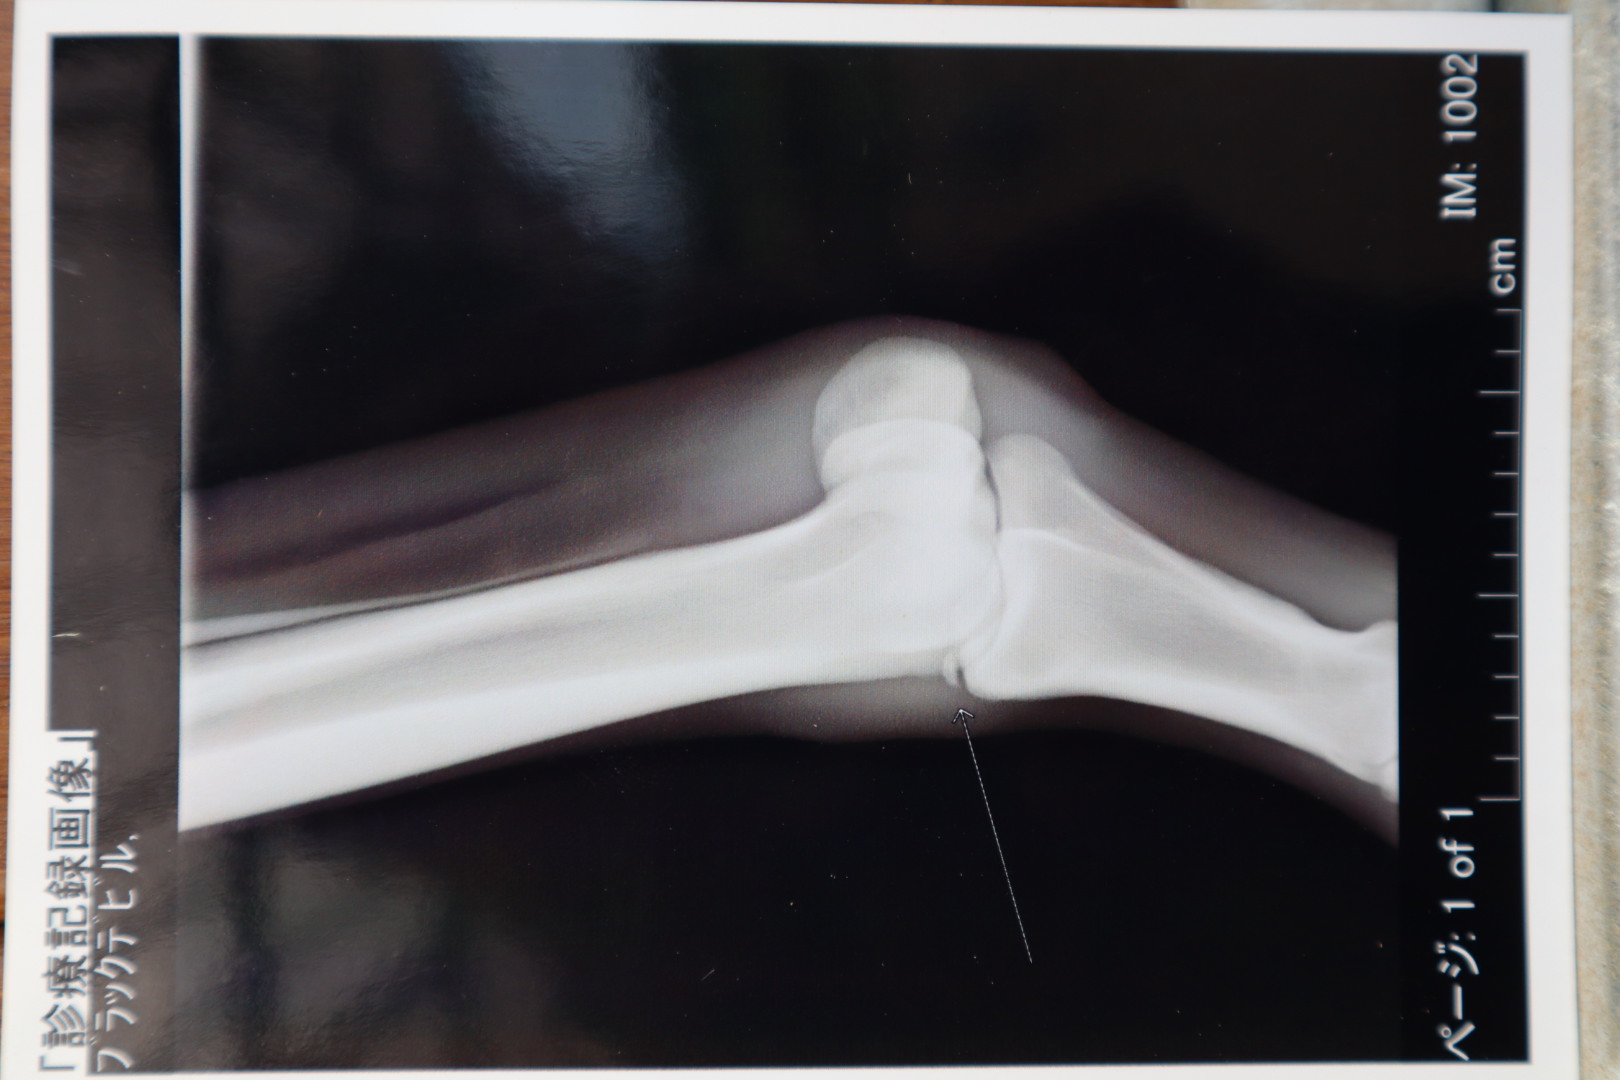

2勝クラスに昇級してからもコンスタントに出走を重ねてキャリアを積みましたが、先日の東京競馬でのレース後に骨折を発症。検査の結果「左前第一指骨骨折により全治3ヵ月」の診断でしたので、このタイミングで出品させていただきます。添付の画像をご確認ください。新たなオーナーの下、新天地での活躍をお祈りいたします。

※2023年5月6日に左前第一指骨骨折を発症。事故見舞金11号(競走中の事故により事故発生の日から3ヵ月以上中央競馬の競走に出走できなくなった場合)の適用を受けています。